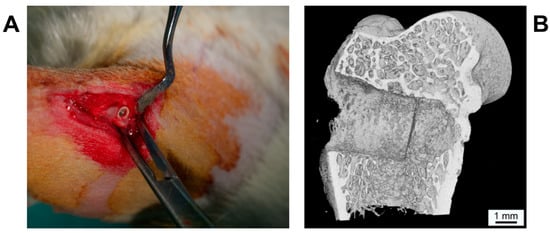

Thirty-six male adult Wistar rats with an average mean body weight of 578.4 g ± 55.6 g were included in the study. The animals were kept at the laboratory with dry food and water ad libitum under standard conditions, including an artificial light–dark cycle of 12 h. All performed surgical interventions were made under general anesthesia with isoflurane (Forene®, AbbVie Germany GmbH and Co. KG, Ludwigshafen, Germany) and intramuscular analgesia via 0.5 mg carprofenum (Rimadyl®, Zoetis Germany GmbH, Berlin, Germany). Following anesthesia, the lateral epicondylus of the femur was exposed via longitudinal incisions at the lateral aspect of the femur. After drilling the implant hole (diameter 3.0 mm, Figure 2) using a sodium chloride cooled implant burr (pilot drill bur G1001 RAXL, Hager and Meisinger GmbH, Neuss, Germany), the implants—randomly chosen by using a computer-generated list—were inserted. In each animal, one implant was inserted on each side, resulting in a total of seventy-two implants (SPI: n = 36; PI: n = 36). After closing periosteum, muscle and skin in layers using absorbable suture material (Vicryl®, Ethicon, Norderstedt, Germany), the animals received intramuscular analgesia via 0.5 mg carprofenum (Rimadyl®, Zoetis Germany GmbH, Berlin, Germany). Additionally, metamizol natrium (Novaminsulfon-ratiopharm®, ratio-pharm GmbH, Ulm, Germany) was applied in the drinking water on a daily basis for the first 5 days postoperatively.

Figure 2. (A) Intraoperative picture of inserted implant in lateral aspect of femur. (B) µCT image of the bony defect in lateral femur condyle with SiO2/HA-coated PEEK implant (SPI), 4 weeks postoperative. The PEEK implant is radiolucent and thus not visible.